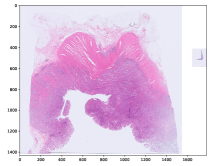

Refer to caption

(a) MSI negative

(b) MSI positive

(c) MSI negative

Figure 3: Three examples of diagnostic slides from the CancerScout Colon dataset. Slides are plotted with an optical magnification of 2.5.

2.1 The CancerScout Colon Data

For this study, we use 208520852085 diagnostic slides from 840840840 colon cancer patients. We have estimated the MSI status of all patients using clinic immunohistochemistry (IHC) based test. A total of 144144144 (17 %times17percent17\text{\,}\mathrm{\char 37\relax}) patients in the cohort are MSI positive. In addition, we have annotated tumor regions in 299299299 slides from 279279279 patients, with the open-source annotation tool EXACT [18]. We use these annotations to train a segmentation model for our reference two-stage approach. Ethics approval has been granted by University Medical Center Goettingen (UMG).

2.1.2 Image Data

The images are magnified H&E stained histological images of formalin-fixed paraffin-embedded (FFPE) diagnostic slides. Images are scanned with an isometric resolution of 0.250.250.25 microns/pixel, which corresponds to a microscopic magnification of 40 ×times4040\text{\,}\times. For all patients, a new slide was freshly cut, stained, and digitalized for this study. Figure 3 shows examples of those slides, we call them cnew slides. For 725725725 patients we have digitalized cold slides. These are archived slides which were cut and stained when the patient was initially treated. Each of the slides is from the same FFPE block as the corresponding cnew, located in very close proximity (about 2 µmtimes2micrometer2\text{\,}\mathrm{\SIUnitSymbolMicro m}). Those slides are used to augment training but not for evaluation. For 274274274 patients we have collected hnew slides. These are slides which only contain healthy tissue taken from the resection margins of the FFPE block. For 246246246 patients we have collected hold slides. These are slides which were cut and stained when the patient was initially treated, located in close proximity (about 2 µmtimes2micrometer2\text{\,}\mathrm{\SIUnitSymbolMicro m}) to the corresponding hnew slide We use those slides to increase the training data for our segmentation model.